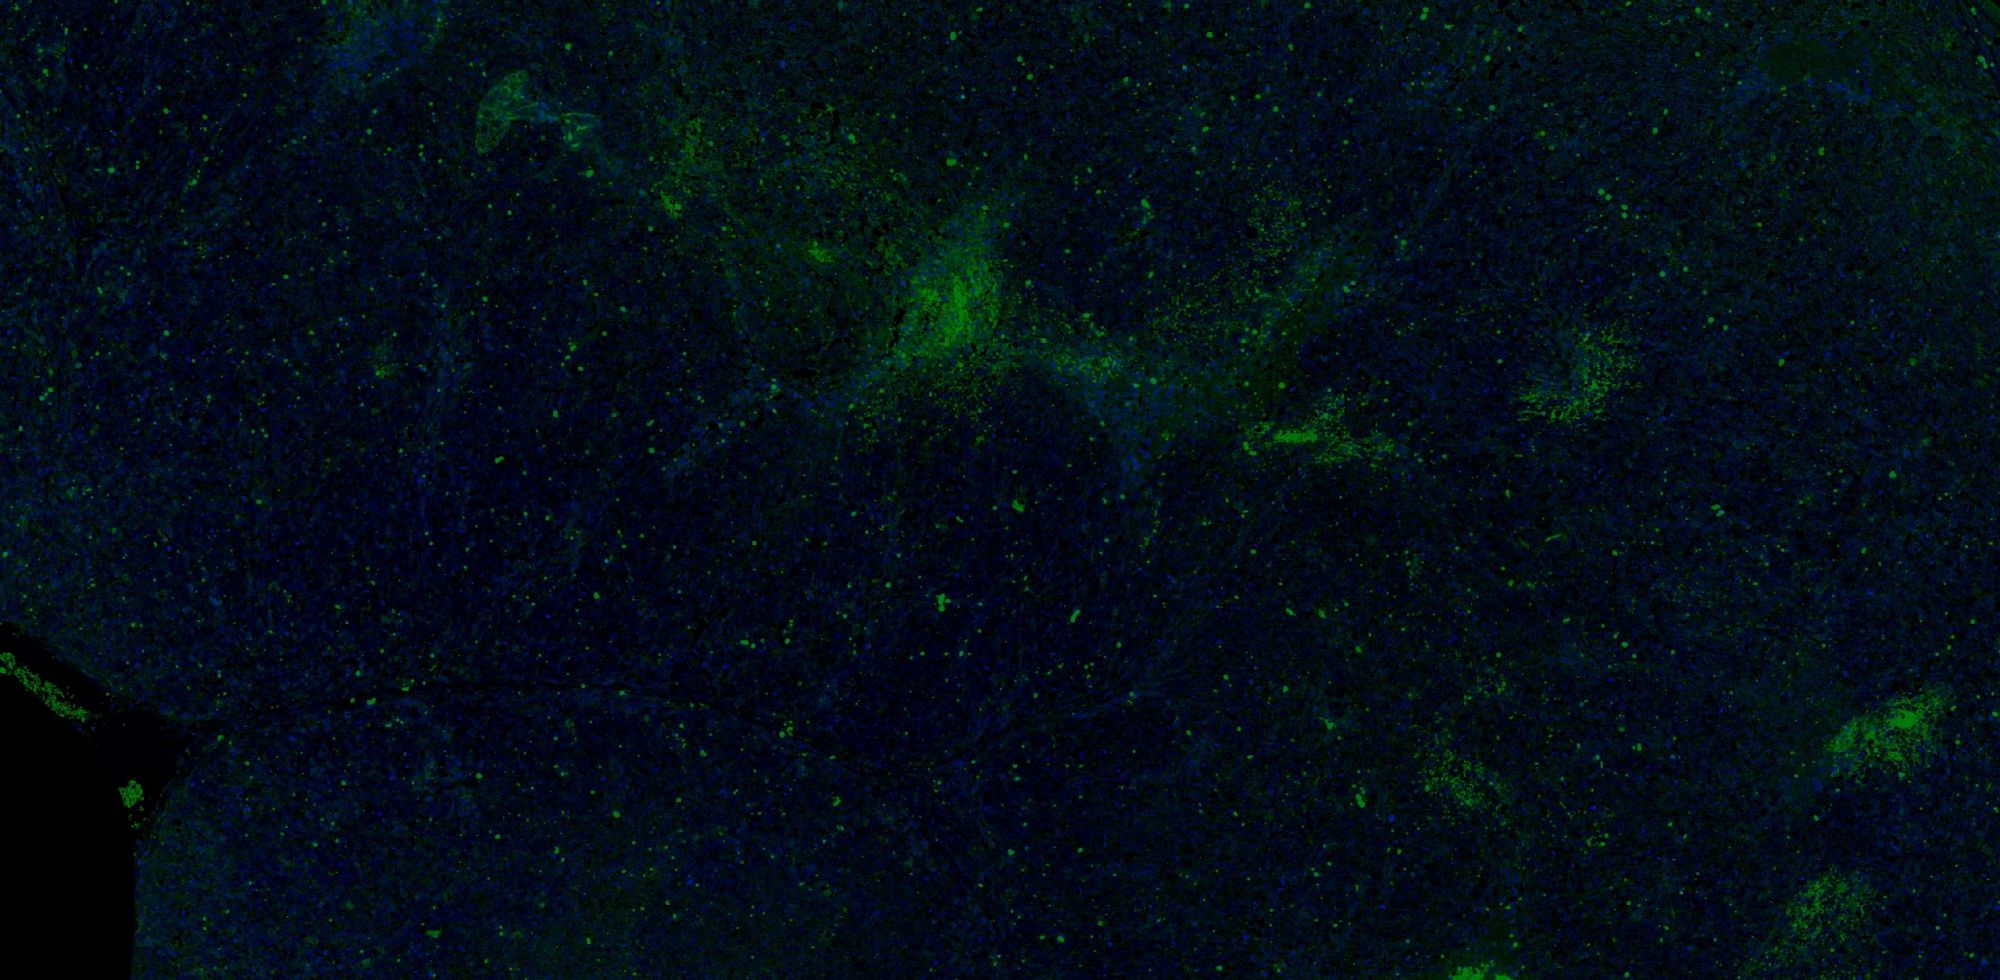

【技術(shù)原理】

免疫學(xué)的基本反應(yīng)是抗原-抗體反應(yīng)。由于抗原抗體反應(yīng)具有高度的特異性,所以當(dāng)抗原抗體發(fā)生反應(yīng)時(shí),只要知道其中的一個(gè)因素,就可以查出另一個(gè)因素。免疫熒光技術(shù)就是將不影響抗原抗體活性的熒光色素標(biāo)記在抗體(或抗原)上,與其相應(yīng)的抗原(或抗體)結(jié)合后,在熒光顯微鏡下呈現(xiàn)一種特異性熒光反應(yīng)。

案例展示